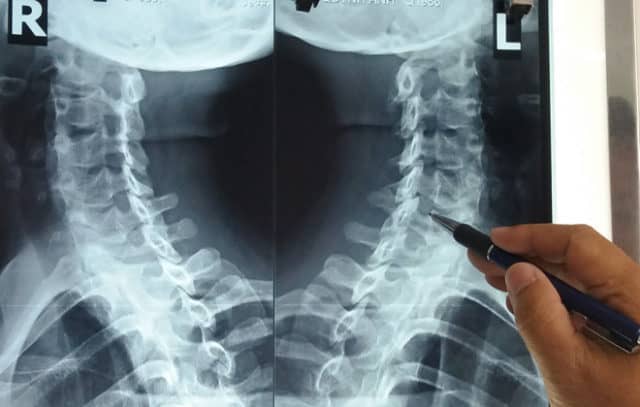

Xét nghiệm hình ảnh: chụp cắt lớp vi tính (CT Scan), chụp cộng hưởng từ (MRI), chụp X-quang để xác định mức độ thoái hóa.